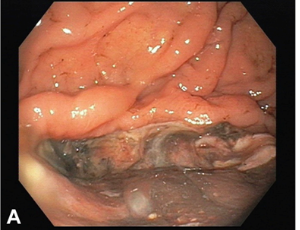

Severe Olmesartan related enteropathy - a case report and literature review

Olmesartan drug-induced enteropathy was first reported 10 years ago. Its physiopathology remains largely unknown and its evocation facing diarrhea is still not systematic, especially in cases of acute and severe diarrhea episodes. In this paper, we report the case of a 71-year-old woman presenting with acute diarrhea associated with complete duodenal mucosal villous atrophy with lymphocytic infiltration.

J Clin Exp Gastroenterol, 2024, Volume Volume 3, Issue Issue 1, p1-4 | DOI: 10.46439/gastro.3.016